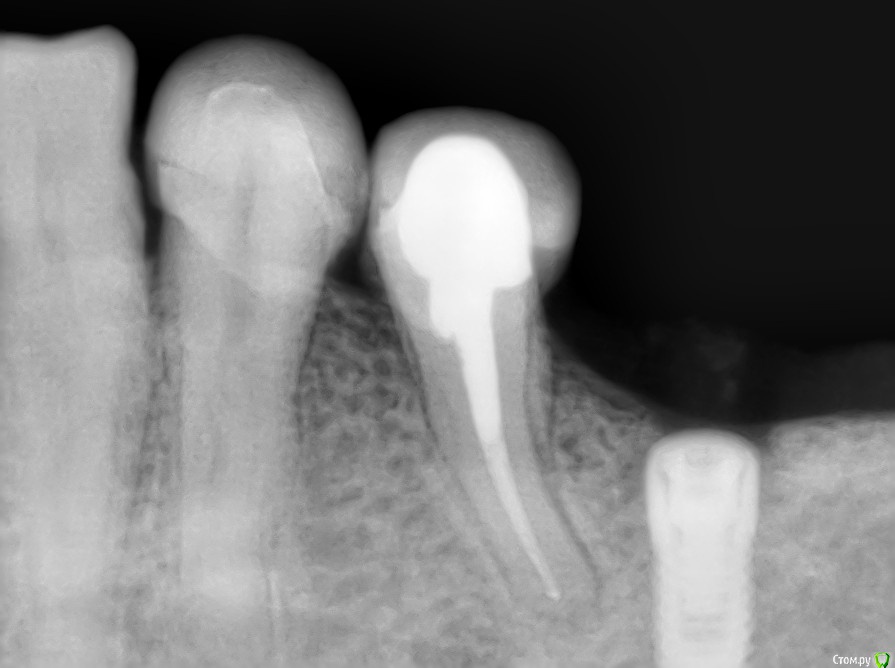

Irouil Опубликовано 28 марта, 2017 Поделиться Опубликовано 28 марта, 2017 Рентгена вообще никакого нет? Я бы обязательно сделал. И отделяемое бы собрал, наверное, и сдал бы на посев. Конкретных данных и клинического опыта нет. Однако... Во первых, логика подсказывает, что цитостатики на регенеративные процессы (а интеграция такой процесс) влияют скорее плохо, чем никак. Далее. Вот тут http://forum.stom.ru/topic/34620-vopros-implantatciia-posle-radioterapii/в обсуждении зацепили бисфосфонаты - они воздействуют на остеокласты почти как цитостатики. Разница только в таргетинге клеток. Ну и напоследок. Беглый пробег по пабмеду дает https://www.ncbi.nlm.nih.gov/pmc/articles/PMC3517327/. Там не клинические исследования, но все же. Чуть бы побольше информации по Вашему кейсу. Ссылка на комментарий

kriokov Опубликовано 1 апреля, 2017 Поделиться Опубликовано 1 апреля, 2017 Ревматоидный и метатрексат.(тоже просил помощи у коллег) Болт в обл 36, суперлайн. фото с коронкой полгода назад ортопед сделалМне кажется свищи, это имплантат коронально "голый ", и слизистая тонкая, хотя всегда возможны другие факторы. 1 Ссылка на комментарий